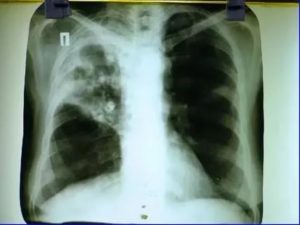

Метатуберкулезный цирроз одного или обоих легких проявляется их уменьшением в размерах, неоднородностью их структуры и расширением бронхов с формированием бронхоэктаз. Также выявляются специфические признаки цирроза в виде кальцинированных очагов в зоне поражения или обызвествления лимфатических узлов.

Чаще всего это заболевание, как и другие метатуберкулезные изменения, выявляется лишь при рентгенологическом исследовании и никак не беспокоит больного.

Метатуберкулезный цирроз легких на рентгене